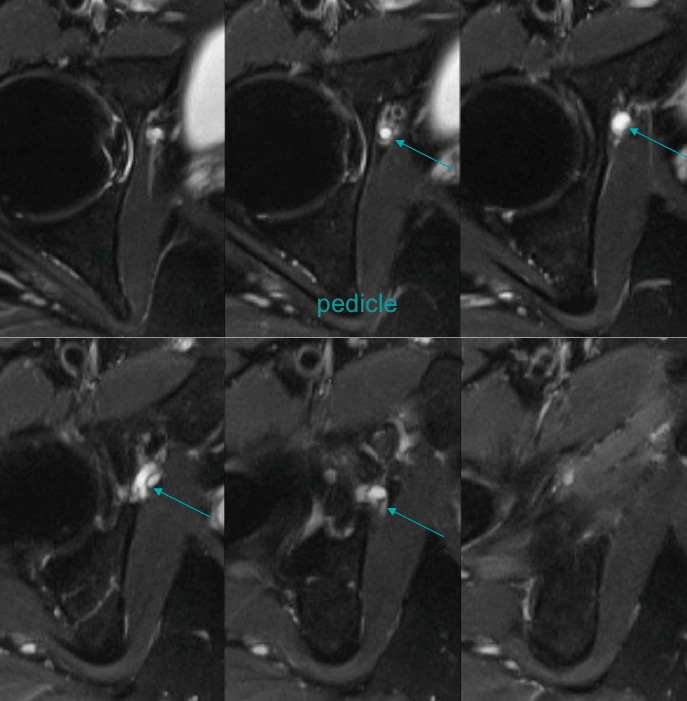

Figure 3 for case Obturator nerve impinge by ganglion cyst

Figure 3

Figure 4 for case Obturator nerve impinge by ganglion cyst

Figure 4